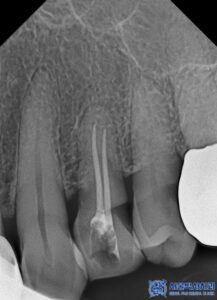

임플란트 치료 외에도, 환자분의 남아있는

치아들 중 심한 충치가 있는 어금니

(오른쪽 위 큰 어금니, 왼쪽 위 작은 어금니,

왼쪽 위 큰 어금니, 왼쪽 아래 큰 어금니)는

신경치료를 진행하였습니다.

특히, 신경치료 시 일반적인 충전재(고무) 대신

MTA 신경치료를 적용하였습니다.

신경치료가 끝난 어금니는 치아를 보호하기 위해

크라운 치료를 진행하였습니다.